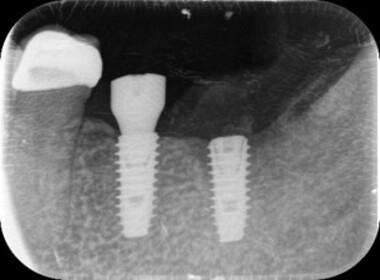

| 0220 #46#47 右下第一第二大臼齒 |

![]() |